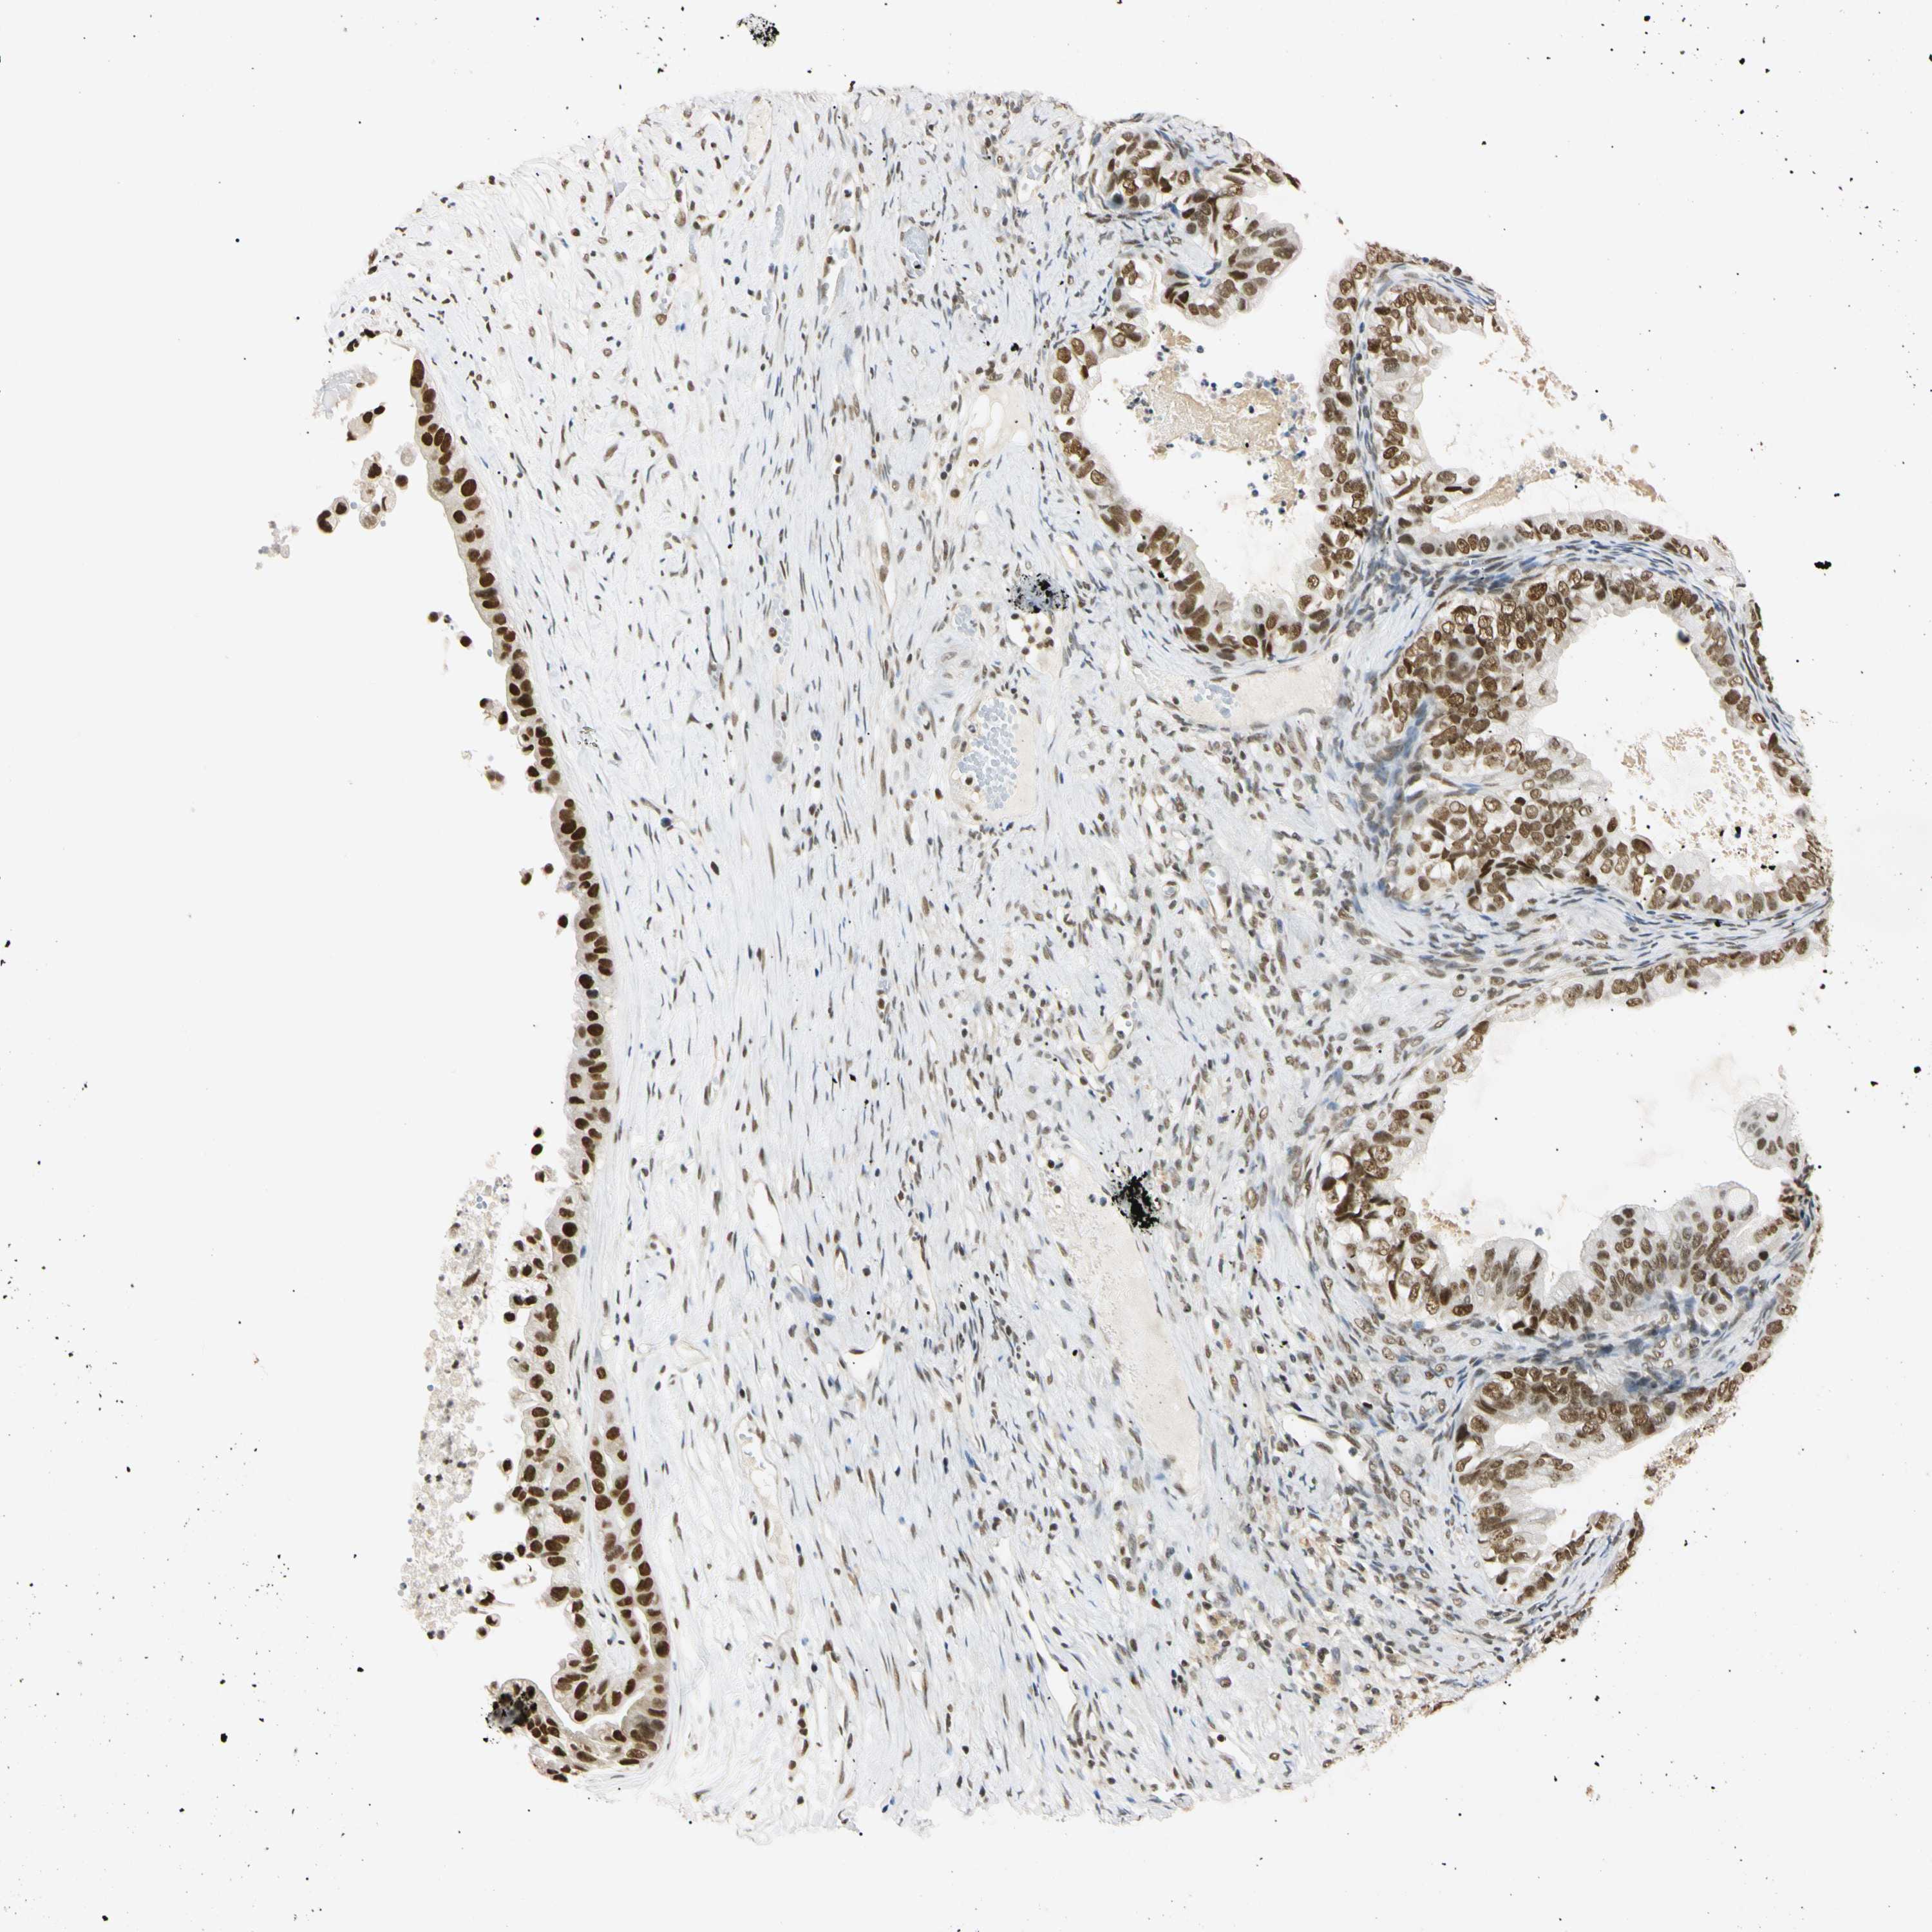

OVARIAN CANCER - Protein expressioni

A mouse-over function shows sample information and annotation data. Click on an image to view it in a full screen mode. Samples can be filtered based on level of antibody staining by selecting one or several of the following categories: high, medium, low and not detected. The assay and annotation is described here.

Note that samples used for immunohistochemistry by the Human Protein Atlas do not correspond to samples in the TCGA dataset.

Antibody stainingi

Antibody staining in the annotated cell types in the current human tissue is reported as not detected, low, medium, or high, based on conventional immunohistochemistry profiling in selected tissues. This score is based on the combination of the staining intensity and fraction of stained cells.

Each image is clickable and will lead to virtual microscopy that enables deeper exploration of all samples and also displays staining intensity scores, fraction scores and subcellular localization as well as patient and tissue information for each sample.

Antibody HPA008751

Antibody CAB005227

Cystadenocarcinoma, serous, NOS